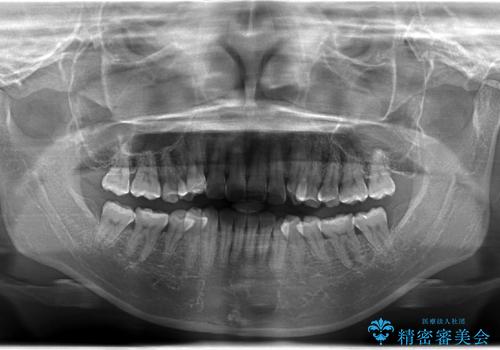

- 非抜歯・遠心移動+IPR+拡大 によるマウスピース矯正を計画した。

八重歯がシビアな場合、抜歯をしないと治せないケースもありますが、奥歯の位置関係を修正したり、歯のサイズダウンを行うことで、抜歯をせずに改善できる場合もたくさんあります。